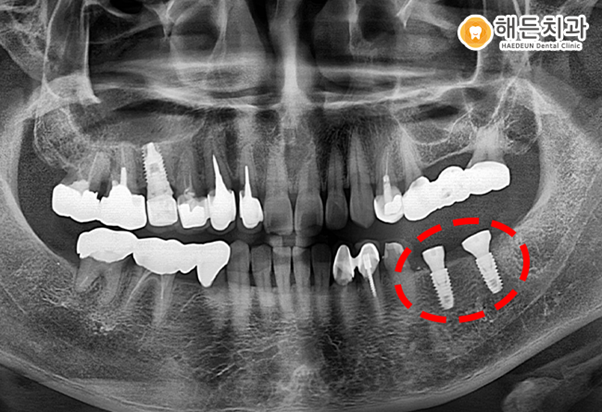

최후방 어금니는 발치를 하고, 기존에 상실된 빈 공간과 함께 당일 임플란트 식립을 도와드렸습니다.

식립 전 잇몸 뼈의 상태, 주변 치아들과의 거리 등을 꼼꼼하게 파악 한 후 진행하였답니다.

일반적으로 발치를 진행하고 나면 뼈가 찰 때까지 기다렸다가 임플란트를 식립 하게 됩니다.

하지만 환자분의 경우 뼈 상태가 양호해 발치 후 즉시 식립이 가능한 경우였습니다.

.

발치 후 즉시 식립을 하게 되면 전체적인 치유 기간을 단축할 수 있고, 골 재생능력을 유도시켜 자연스럽게 골유착이 진행됩니다.

하지만 모든 경우에 이렇게 즉시 식립이 가능한 것은 아니기 때문에, 정밀한 검진과 전문가와의 충분한 상담을 통해 진행을 하게 됩니다.